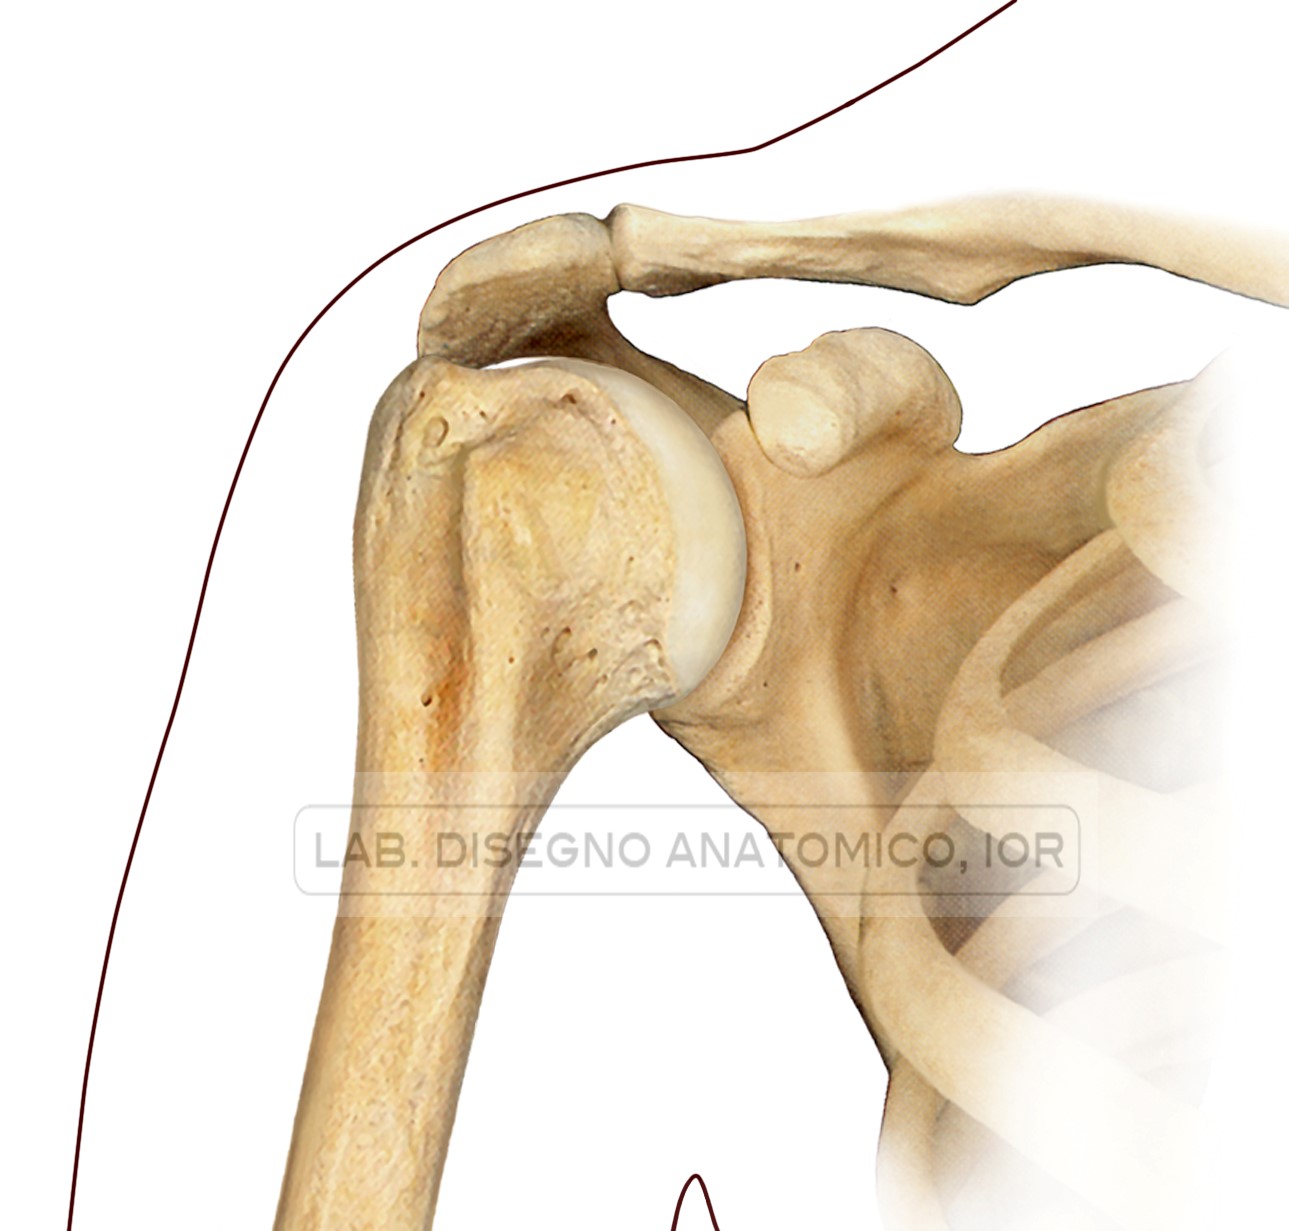

L’articolazione della spalla (scapolo-omerale) è costituita dalla testa dell’omero, che ha la forma di una porzione di sfera, e dalla cavità glenoidea (o glena) della scapola, che ha forma vagamente ovale ed è poco profonda (fig. 1).